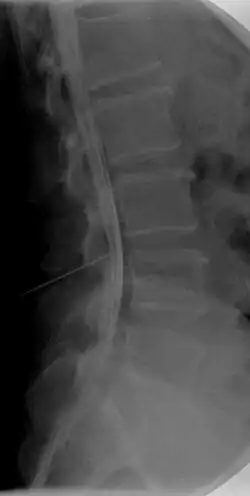

Caudografie

Caudografie is in de geneeskunde een onderzoeksmethode waarbij de cauda equina in beeld wordt gebracht door het onderste deel van het ruggenmergskanaal met contrastvloeistof te vullen door middel van een lumbale punctie en dan röntgenfoto's te nemen. Op deze manier kan meestal de oorzaak van een caudasyndroom in beeld gebracht worden.